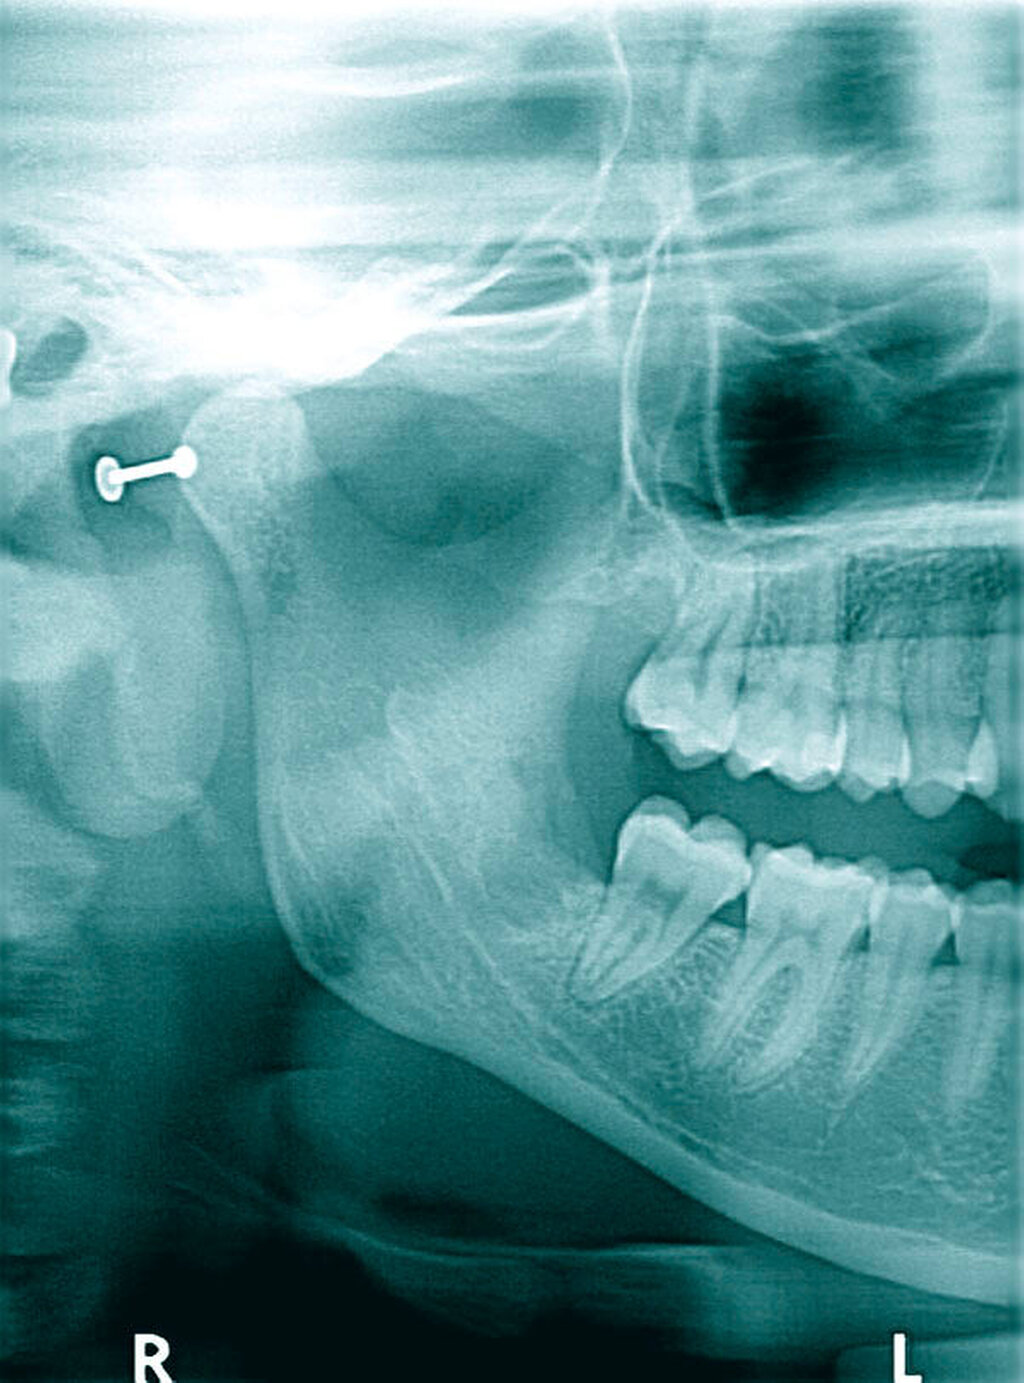

Innerhalb der nächsten acht Wochen, unter laufender oraler Antibiotikatherapie, kam es zunächst erneut zu einer Beschwerdebesserung. Als plötzlich wieder stärkere Schmerzen im Unterkiefer auf der rechten Seite auftraten, zeigte sich im erneuten OPG nun eine Osteomyelitis in regio 048 bis zum Processus muscularis (Abbildung 3). Hier wurde stationär, unter intravenöser Antibiose, die Dekortikation, die Entfernung des gelockerten und schmerzhaften Zahns 47, die Einlage von Gentamycinschwämmchen und plastische Deckung durchgeführt, sowie eine naso-gastrale Ernährungssonde appliziert. Auf eine Kontinuitätsresektion und Anlage einer Reko-Platte konnte zunächst verzichtet (Abbildung 4) werden.

Im weiteren Verlauf von 2016 bis Anfang 2017 erfolgten aufgrund rezidivierender Beschwerden eine hyperbare Sauerstofftherapie (HBO) in der Uniklinik in Düsseldorf und auch eine weitere Dekortikation in der MKG-Abteilung der Kollegen. Die regelmäßigen OPG-Kontrollen in der Zeit zeigten eine sklerosierende Osteomyelitis beziehungsweise eine Sklerosierung der Mandibula (Abbildung 5).